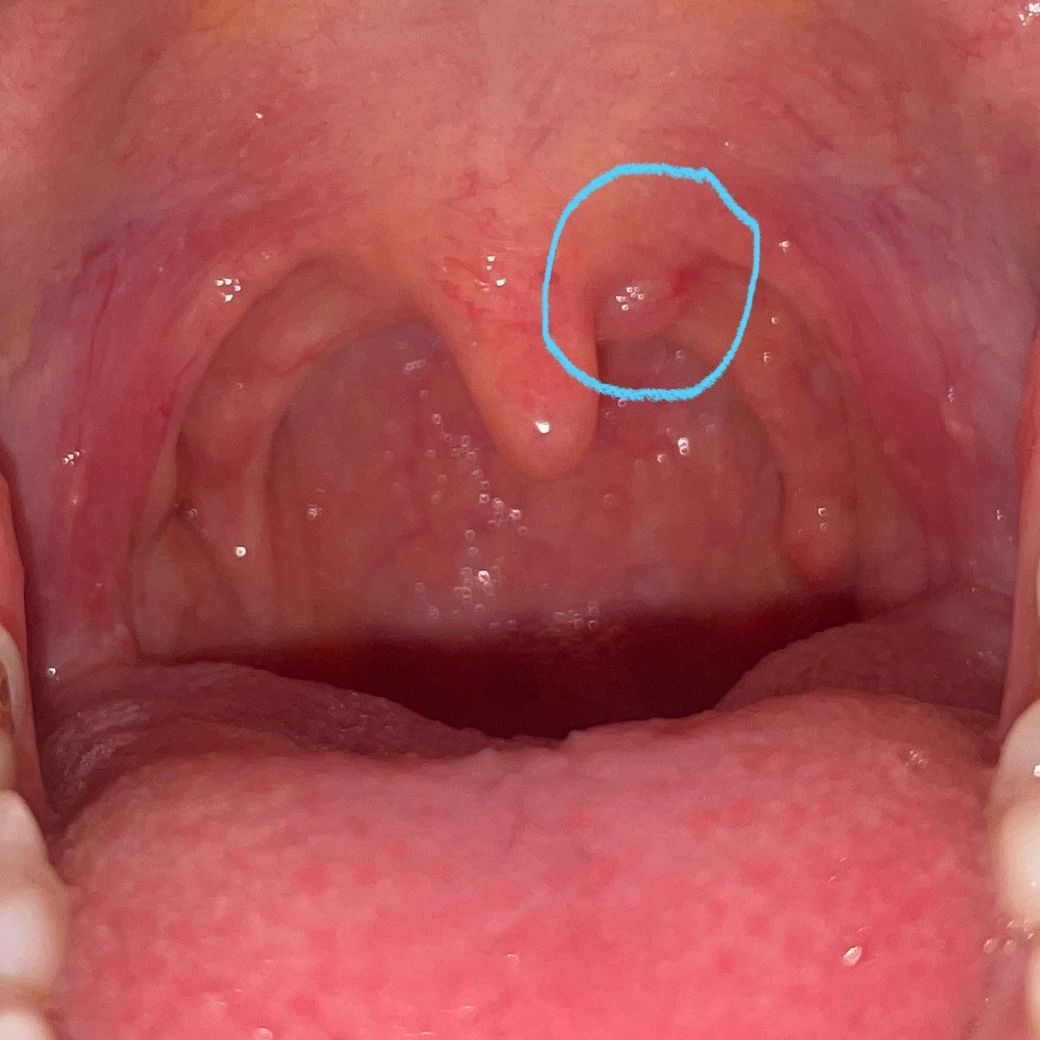

갑자기 목젖 옆에 생긴 종양?같은게 신경쓰여 질문드립니다. 오늘 면봉으로 건드려봤는데 달랑달랑하더군요

꽤 예전부터 있었는데(1년 전쯤?) 별다른 증상은 없습니다.제거해야하는 종양인가요?

모양과 색상 등으로 미루어 볼 때 , 종양일 가능성은 낮은 것으로 보입니다.

크기가 점차 커지는 것이 아니라면 경과관찰 하여도 문제가 없을 것으로 생각됩니다.

만일 크기가 점차 커진다면, 이비인후과에 내원하시어 상담을 받아보시기를 권유드립니다.